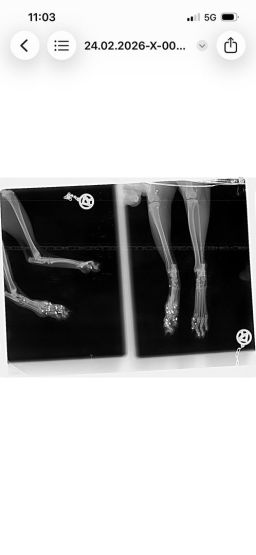

Nach diesem Zwischenfall waren alle vier Katzen verschwunden. Die Betreuerinnen suchten jeden Tag und stellten schließlich eine Kamera auf. Es wurde auch nochmals Kontakt mit dem Jäger aufgenommen – die Ungewissheit war unerträglich, man bat ihn um Ehrlichkeit, in der Hoffnung, Gewissheit zu bekommen und die Suche einstellen zu können. Doch der Jäger stritt weiterhin ab, auf die Katzen geschossen zu haben. Die Suche nach den Katzen ging also weiter, bis schließlich eines Tages eine der verschollenen Katzen auf den Kamera-Aufnahmen zu sehen war, zwei Wochen später tauchte eine zweite Katze auf den Aufnahmen auf. Nach insgesamt sechs Wochen Suche konnten zwei der Katzen endlich gesichert werden. Doch beim Tierarzt der nächste Schock: eine der Katzen war von mehreren Schrotkugeln getroffen worden und musste starke Schmerzen haben.

Nach Auswertung der Röntgenbilder liegt der Schluss nahe, dass die Katze von unten beschossen worden sein muss – die Betreuerinnen erzählen, dass die Katzen immer gerne auf den Balken im Stadl geschlafen haben. Es ist also ziemlich klar, was da passiert sein muss – und es stellt sich die Frage, wie abgebrüht man sein muss, um zu so etwas fähig zu sein. Bei einer Katze wurden die Kugeln, die unmittelbar unter der Haut lagen, mittlerweile entfernt – die tieferliegenden Kugeln sollen erst dann entfernt werden, wenn sie der Katze Probleme bereiten. Man will die Katze im Moment nicht noch mehr stressen. Der Kater, der ebenfalls gesichert werden konnte, ist bis heute so stark traumatisiert, dass eine Untersuchung bisher noch gar nicht durchgeführt werden konnte. Zumindest waren bei ihm aber keine Kugeln unter der Haut zu ertasten. Von den beiden anderen Katzen, die an der besagten Futterstelle versorgt worden waren, fehlt bis heute jede Spur. Es ist leider davon auszugehen, dass sie es nicht geschafft haben.

Hier noch weitere Röntgenbilder der angeschossenen Katze und das Schreiben der Staatsanwaltschaft Augsburg: